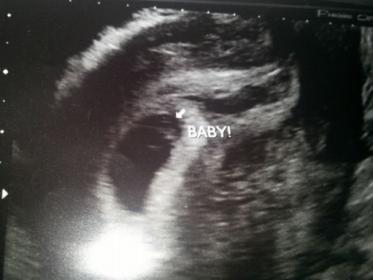

hello please guess gender of my current pregnancy the first is an abdominal scan 7 weeks 3 days

Attachment 20400